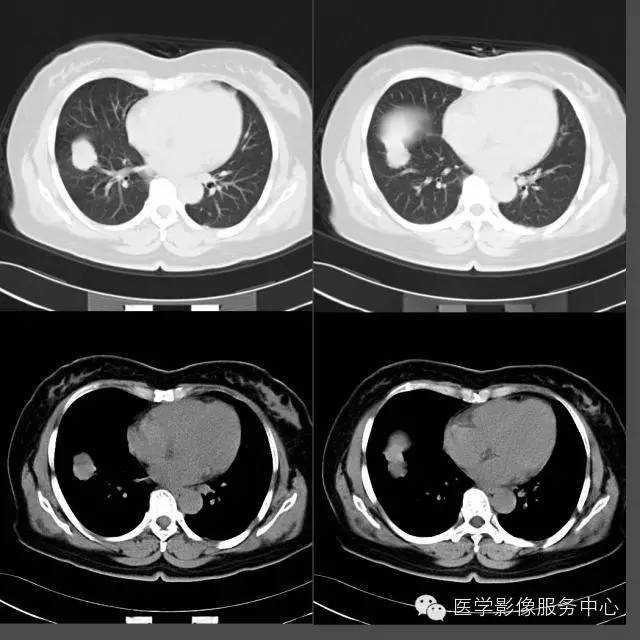

CT上表现的结节或肿块影像在病理组织学上为肿瘤的乳头状结构,以及破坏、扭曲的肺组织;磨玻璃样阴影代表肿瘤细胞沿肺泡壁生长或阻塞肺泡腔引起的阻塞性肺炎;

肺乳头状腺癌生长方式与肺泡癌相似,结节或肿块影周围出现的卫星灶能对应病理组织学上的阻塞性肺炎、支气管炎、细支气管脓肿等改变。这种磨玻璃样改变在肺腺癌病例中普遍可以看到,但在其他类型肺癌中比较少见。

空洞、钙化在肺乳头状腺癌中几乎见不到。

“空泡征”、“空气支气管征”在肺乳头状腺癌病例中大部分可以看到,但边缘光滑、境界清楚;而其他类型肺癌即使出现这些征象,其边缘境界往往不清楚,这一点是和其他类型肿瘤所不同的。